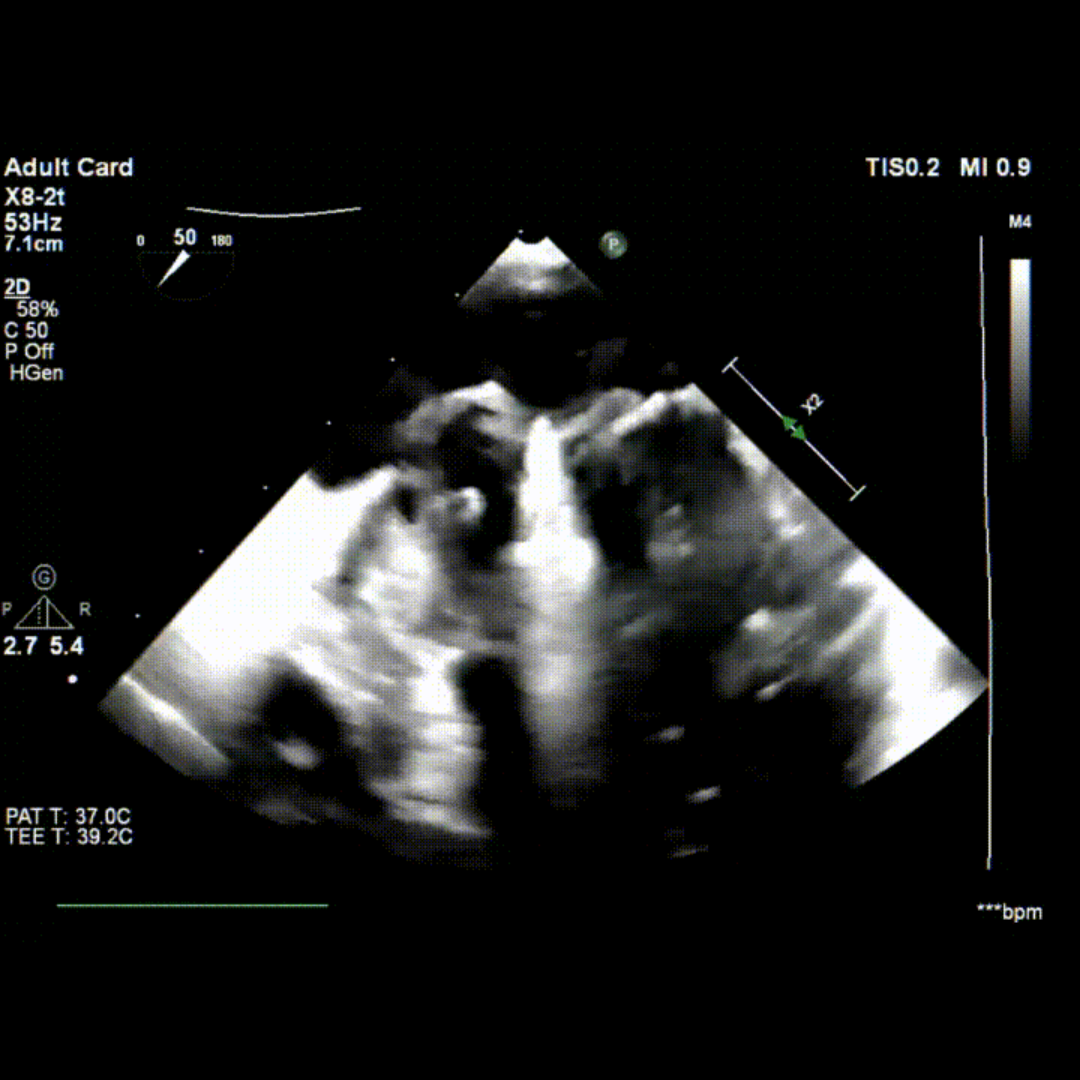

术前TEE影像

术中TEE影像